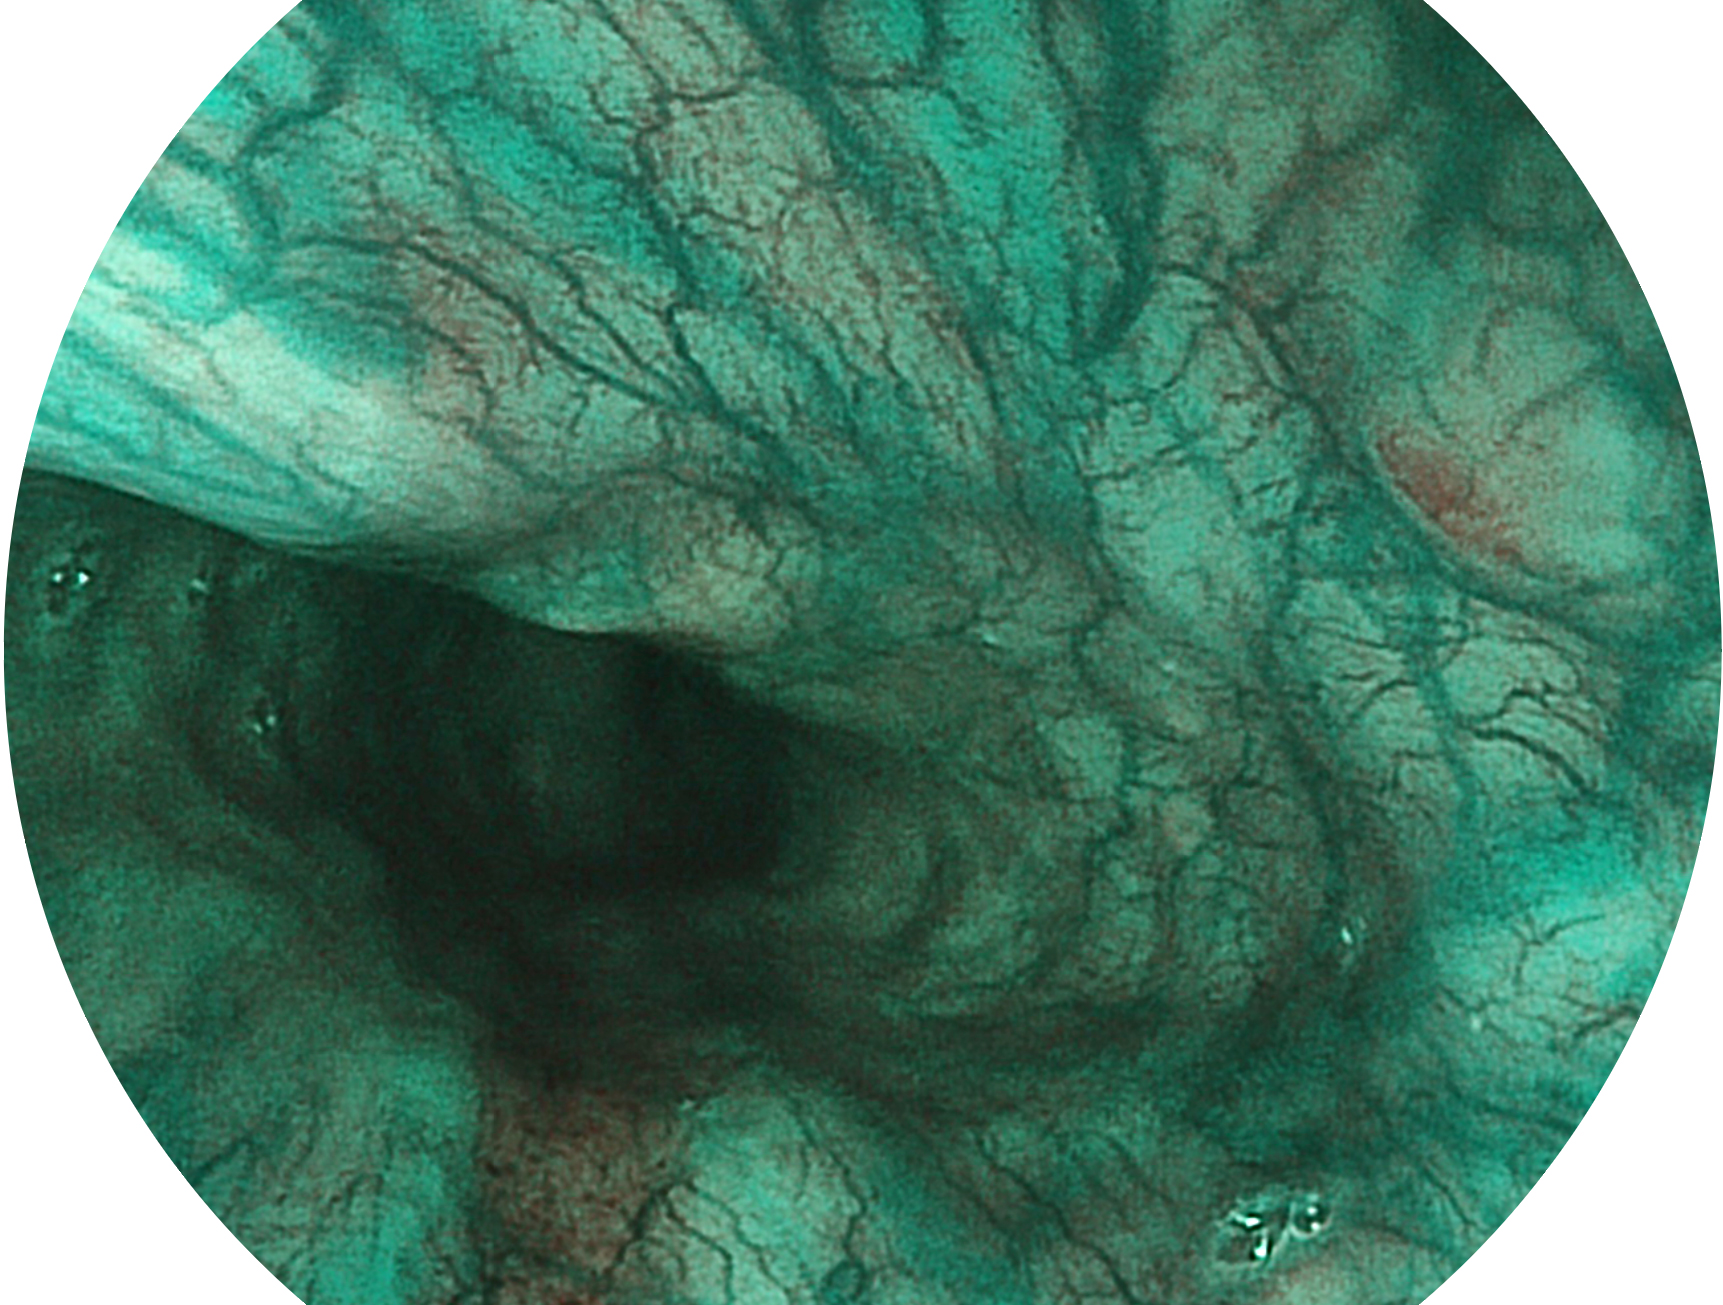

開立新開發(fā)的內(nèi)鏡染色技術(shù),主要是基于多波長(zhǎng)LED 光源的開發(fā),VLS-55Q 四波長(zhǎng)LED 光源是由四個(gè)不同顏色的LED光按照相應(yīng)照明模式所規(guī)定的特定發(fā)光比例進(jìn)行合束后形成,合束后形成的照明光的光譜由紅光、綠光、藍(lán)光及藍(lán)紫光這四個(gè)不同的波段范圍構(gòu)成。具有更高光譜自由度,通過(guò)光譜比例的控制,實(shí)現(xiàn)了聚譜成像技術(shù),英文全稱為“Spectral Focused Imaging, SFI”,縮寫為“SFI”和光電復(fù)合染色成像技術(shù),英文全稱為“Versatile Intelligent Staining Technology, VIST”,縮寫為“VIST”。